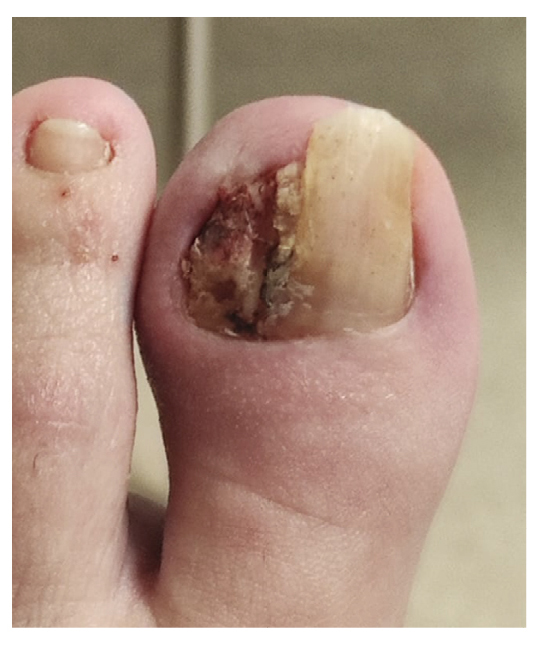

Tras empeoramiento del cuadro clínico, el 14 de noviembre de 2022 se realiza en su centro de salud la retirada parcial de la placa ungueal lateral del pie izquierdo junto con raspado, retirando tejido hiperqueratósico y de granulación. El procedimiento es repetido 48 h más tarde (16 de noviembre de 2022) por no haber retirado toda la lesión (Figura 3), cambiando el tratamiento antibiótico a anaclosil 500 mg 1/6 h y posteriormente a ciprofloxacino 500 mg 1/12 h durante las siguientes semanas.

Figura 3. Semana 8. Resección parcial de tejido hiperplásico realizado en su centro de salud.

La paciente presenta inicialmente mejoría del dolor, aunque nunca termina de ceder completamente (Figura 4). Refiere recurrencia de la lesión ungueal lo que le lleva a consultar una segunda opinión a las 6 semanas de la intervención con otro podólogo. Este último con fecha 27 de diciembre (Figura 5) realiza cultivo bacteriano de la lesión, resultando negativo, y también valoración de la lesión mediante ecografía (sin informe). El 13 de enero la paciente es intervenida quirúrgicamente mediante técnica fenol-alcohol en el borde lateral del primer dedo del pie izquierdo (Figura 6).

Figura 4. Semanas 9-14. Recurrencia progresiva de la lesión tras resección parcial.